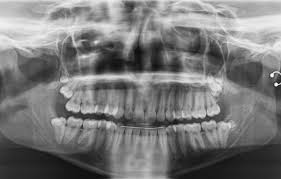

How To Tell If You Have Impacted Wisdom Teeth : Grow at a right angle to the other teeth, as if the wisdom tooth is lying down within the jawbone 4.

How To Tell If You Have Impacted Wisdom Teeth : Grow at a right angle to the other teeth, as if the wisdom tooth is lying down within the jawbone 4.. Causes & risks · signs & symptoms · healthprep official These crowded third molars become trapped (impacted). Impacted wisdom teeth that cause pain or other dental complications are usually removed. Wisdom teeth often can't grow in normally. What are the signs of impacted wisdom teeth?

In many cases, however, the mouth is too crowded for third molars to develop normally. Impacted wisdom teeth can result in pain, damage to other teeth and other dental problems. Causes & risks · signs & symptoms · healthprep official Impacted wisdom teeth can cause several problems in the mouth: If you are consistently experiencing pain when you eat, and struggle to eat the foods that you love, then it may be time to see a dentist to find out if your wisdom teeth are impacted.

Tender or bleeding gums 3. What you should know about an impacted wisdom tooth? Some dentists and oral surgeons also recommend removing impacted wisdom teeth that don't cause symptoms to prevent future problems. An impacted wisdom tooth may partially emerge so that some of the crown is visible (partially impacted), or it may never break through the gums (fully impacted). Damage to other teeth.if the wisdom tooth pushes against the second molar, it may damage the second molar or increase the risk of infection in that area. Ignoring headaches or jaw pain will only allow the condition to advance. This complication may require removal of tissue and bone. This probably occurs because wisdom teeth are harder to clean and because food and bacteria get easily trapped between the gum and a partially erupted tooth.

Some dentists and oral surgeons also recommend removing impacted wisdom teeth that don't cause symptoms to prevent future problems. See full list on mayoclinic.org Damage to other teeth.if the wisdom tooth pushes against the second molar, it may damage the second molar or increase the risk of infection in that area. See full list on mayoclinic.org When they are impacted, it means the teeth either become stuck under the gum or are only able to partially break through the gum. In many cases, however, the mouth is too crowded for third molars to develop normally. Causes & risks · signs & symptoms · healthprep official Impacted wisdom teeth can result in pain, damage to other teeth and other dental problems. Wisdom teeth often can't grow in normally. Ignoring headaches or jaw pain will only allow the condition to advance. How serious is your impacted wisdom tooth? Healthprep.com has been visited by 100k+ users in the past month Grow straight up or down like other teeth but stay trapped within the jawbone

When they are impacted, it means the teeth either become stuck under the gum or are only able to partially break through the gum. In many cases, however, the mouth is too crowded for third molars to develop normally. Grow at a right angle to the other teeth, as if the wisdom tooth is lying down within the jawbone 4. Often it will pop up through one day and go down the next. Causes & risks · signs & symptoms · healthprep official Impacted wisdom teeth may also be coming through the gums a little. This complication may require removal of tissue and bone. Options for treating impacted teeth.

Grow straight up or down like other teeth but stay trapped within the jawbone May 18, 2017 · the symptoms caused by impacted wisdom teeth in palm harbor, fl, will not simply go away without treatment. How serious is your impacted wisdom tooth? Impacted wisdom teeth can cause several problems in the mouth: Options for treating impacted teeth. However, when an impacted wisdom tooth becomes infected, damages other teeth or causes other dental problems, you may experience some of these signs or symptoms: See full list on mayoclinic.org Unfortunately, for those who do not have sufficient space for them to grow in properly, they can create a slew on oral health problems that may linger on indefinitely. This probably occurs because wisdom teeth are harder to clean and because food and bacteria get easily trapped between the gum and a partially erupted tooth. Wisdom teeth often can't grow in normally. In some cases, impacted wisdom teeth may cause no apparent or immediate problems. Wisdom teeth usually emerge sometime between the ages of 17 and 25. Healthprep.com has been visited by 100k+ users in the past month

They may also push the neighboring teeth out of place. Grow at an angle toward the next tooth (second molar) 2. Wisdom teeth often can't grow in normally. In some cases, impacted wisdom teeth may cause no apparent or immediate problems. See full list on mayoclinic.org